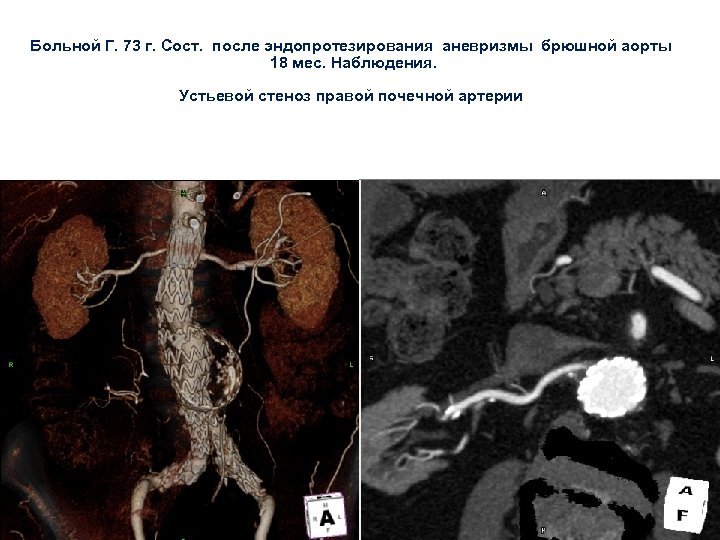

Больной Г. 73 г. Сост. после эндопротезирования аневризмы брюшной аорты 18 мес. Наблюдения. Устьевой стеноз правой почечной артерии

Больной Г. 73 г. Сост. после эндопротезирования аневризмы брюшной аорты 18 мес. Наблюдения. Устьевой стеноз правой почечной артерии